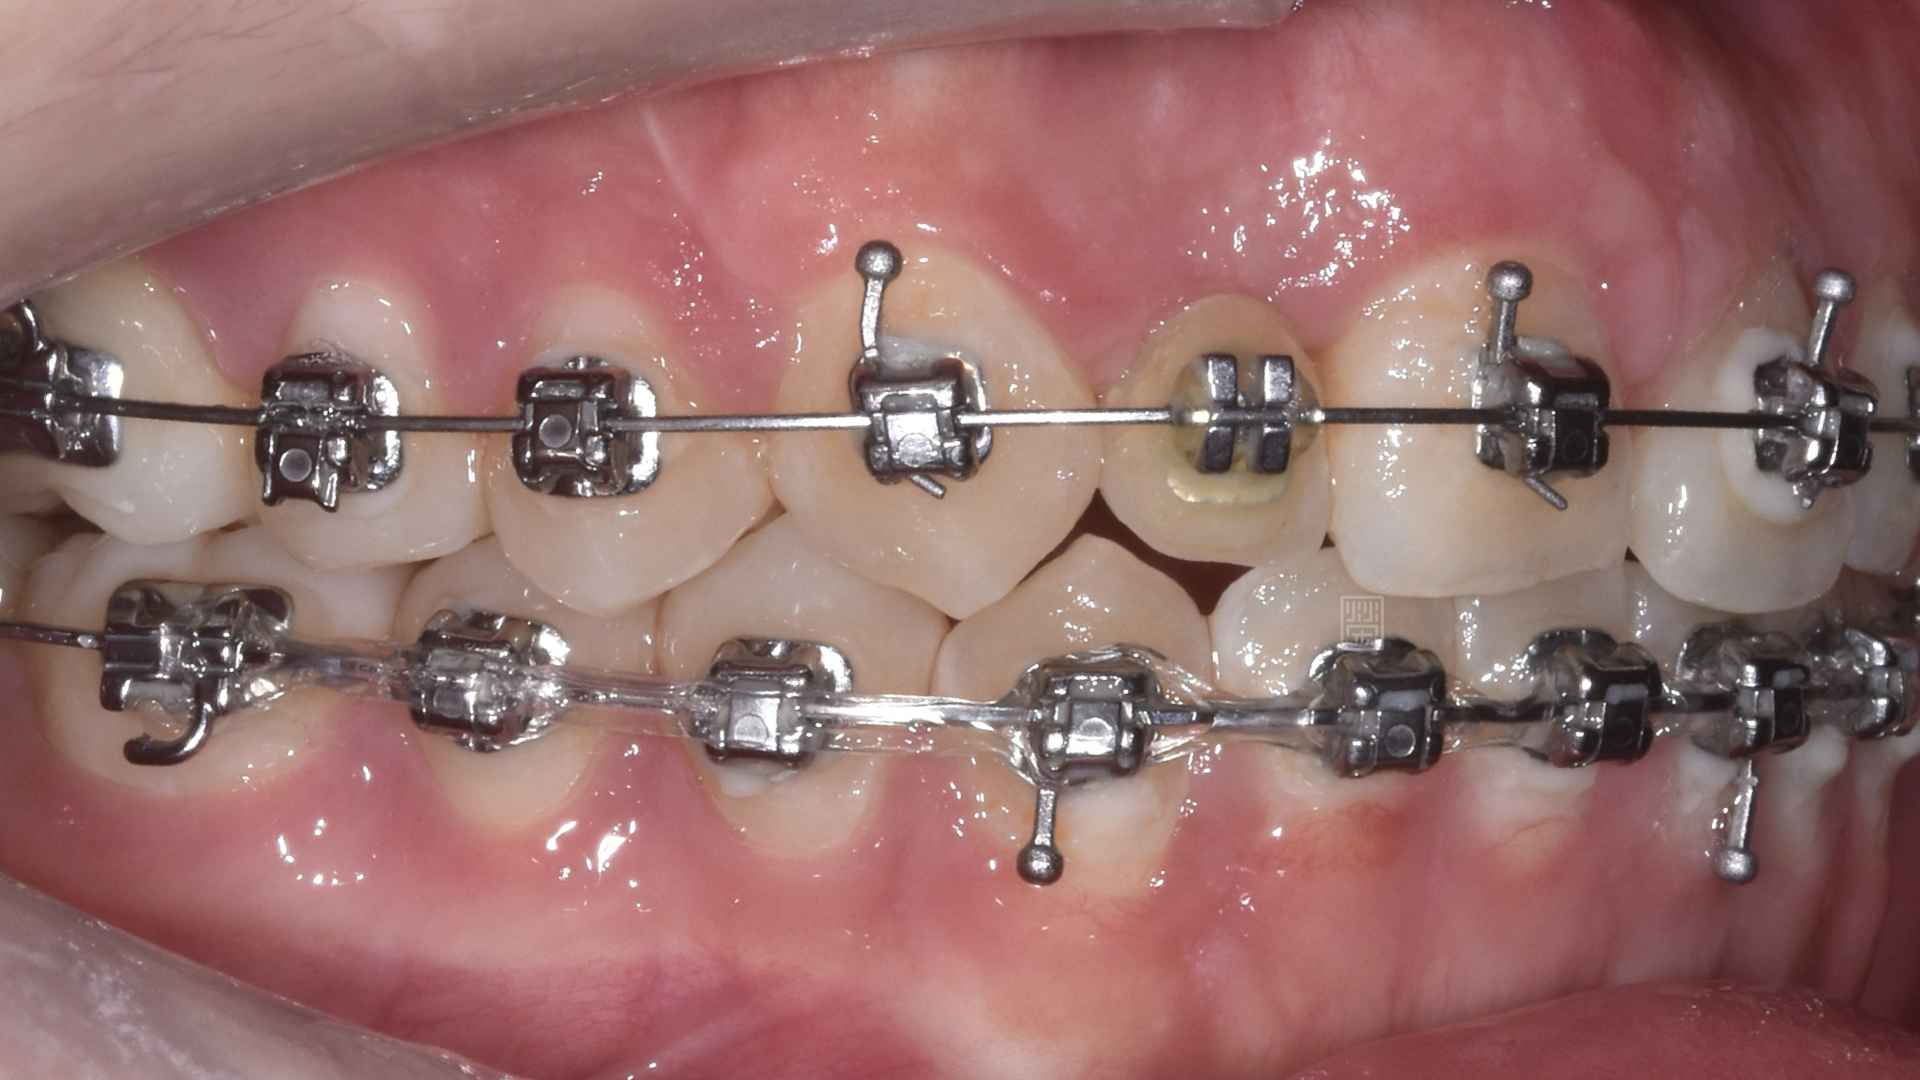

矯正移出側門牙空間

矯正時因牙齒沾黏骨頭無法移動

長期缺牙側門牙空間不足

首先張馨文醫師先將牙齒重新排列,但是在門牙的部分因為先前外傷關係,牙齒發生沾黏的狀況,牙齒移動度很小,吳禕凡醫師藉由皮質骨手術加上術後立即施力,將門牙拉至中央位置,並且給側門牙植牙適當空間。